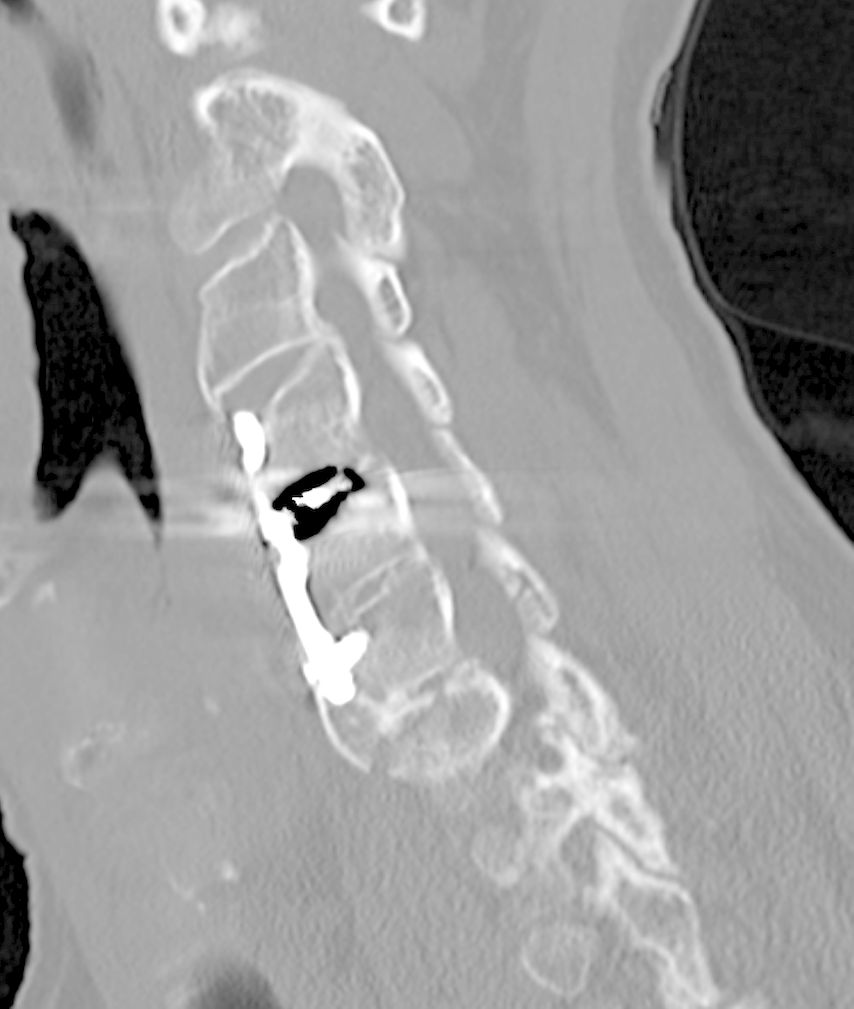

Beispiel für die Implantation zervikaler Pedikelschrauben. In diesem Fall kam es bei einem 61-jährigen Patienten 10 Jahre nach anteriorer zervikaler Diskektomie und Fusion (ACDF) C4/5 und ventraler Verplattung C4–6 zu einer Ankylosierung auch von C6/7. Nach Sturz kam es zu einer Fraktur bei C6/7 mit begleitender Bogenfraktur und auch Beteiligung der dorsalen Ligamenta (Abb. 1 und 2). Klinisch bestanden ausgeprägte Nackenschmerzen und kein neurologisches Defizit. Es wurde die Indikation der dorsalen Verschraubung von C4 auf Th1 gestellt. Intraoperativ wurde routinemäßig zusätzlich eine kleine Referenzschraube in einer Lamina – entfernt von der Dornfortsatz-Referenzklemme für die Navigation – gesetzt. Mit dieser konnte intraoperativ die Genauigkeit der Navigation exakt überprüft werden (Abb. 4 und 5). Mittels navigierter High-Speed-Fräse wurden die Schraubenkanäle vorgebohrt (Abb. 6), im Anschluss wurde der Bohrkanal ausgetastet und die Schrauben wurden implantiert. Abbildung 7 zeigt eine Röntgenkontrolle 3 Monate postoperativ.